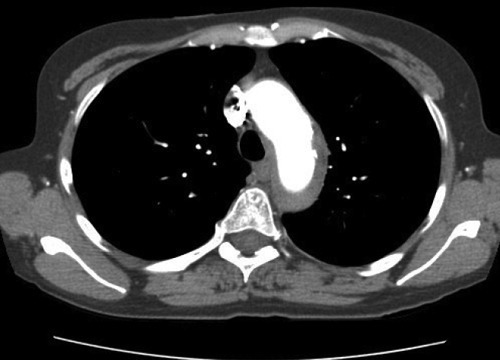

- Рентген грудной клетки в прямой и боковой проекциях. На снимках хорошо видны крупные сосуды, по виду которых врач делает вывод о наличии патологии. При утолщении аорты меняется ее изгиб, удлиняется тень. По этим признакам специалист определяет величину закупоривания.

- МРТ. Магнитно-резонансная томография — информативный способ получения изображения с использованием магнитного резонанса. Позволяет получать развернутую визуальную картину имеющейся патологии.

- Ангиография. Метод исследования кровеносных сосудов с помощью введения контрастного вещества. Дает возможность получить сведения о заполняемости аорты кровью, работе клапанов.

- Информативным является рентгенографическое исследование, флюорография. Аорта уплотнена (что это значит и почему развивается, вы уже знаете), ее тень на снимке удлинена, возможно появление патологического разворота или нехарактерного изгиба по ходу сосуда.

- Золотым стандартом на сегодняшний день является контрастная ангиография. Во время этой процедуры врач может изучить особенности кровотока, увидеть те или иные отклонения.

- Рентгенографический снимок грудной полости в прямой и боковой проекциях. Врач-рентгенолог сможет разглядеть на снимке характерные изменения, подтверждающие патологию. Если подозревается изменение в брюшной части аорты, то делают снимок брюшной полости.

- Ультразвуковое исследование, допплерография. Эти методы позволяют более точно и локализованно изучить поврежденный участок сосуда, а также выявить нарушения кровообращения и изменения во внутренних органах, если таковые присутствуют.

- Магнитно-резонансная томография.

- Контрастная ангиография.